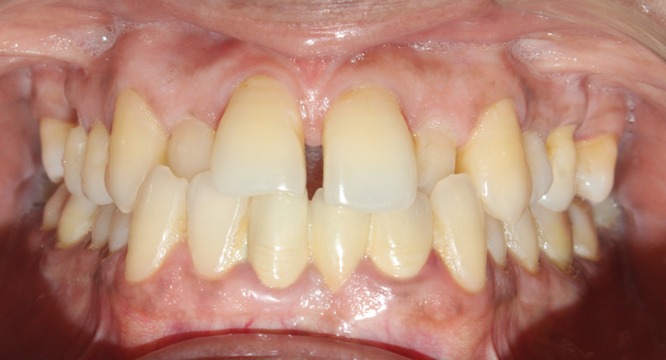

Before & After Results

At Aline Dent, we take pride in delivering visible and lasting improvements in our patients’ smiles. Our before-and-after results highlight the effectiveness of modern dental treatments combined with personalized care. This gallery showcases real dental cases treated at our clinic, giving you a clear idea of how different dental concerns can be corrected with the right treatment approach.

From minor corrections to complete smile enhancements, these teeth transformation results demonstrate how professional dental care can improve both oral health and appearance. Our experienced dental team carefully evaluates each patient’s needs and creates customized treatment plans to achieve natural, healthy, and confident smiles.

In this gallery, you will find a variety of smile makeover cases, including treatments for crooked teeth, gaps, discoloration, damaged teeth, and other common dental concerns.